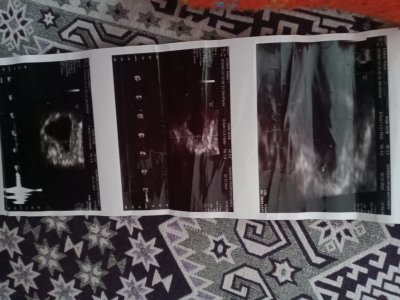

Kese şekline göre cinsiyet tahmini

Senin erekekMerhabaaşuan 10 haftalık çok erken biliyorum sadece sormak istedim cinsiyet tahmin edebilir misiniizz

Kız seninde

kesenin şeklinden mi bebeğin duruşundan mı anlıyorsunuz acabaSenin erekek

Doktor bi şey dedi mi bilmiyorm ama kız sankiBana da bakarmisiniz lütfen

Erkeğe benziyor dediDoktor bi şey dedi mi bilmiyorm ama kız sanki

Benimkine bi tahmin edermisiniz 9+2 haftalikSenin erekek

Kız gibi ya sankiBenimkine bi tahmin edermisiniz 9+2 haftalik

Ya bana da bakar mısınız 9 haftalık çok merak ediyorum neye göre anliyosunuz :)Merhabaaşuan 10 haftalık çok erken biliyorum sadece sormak istedim cinsiyet tahmin edebilir misiniizz